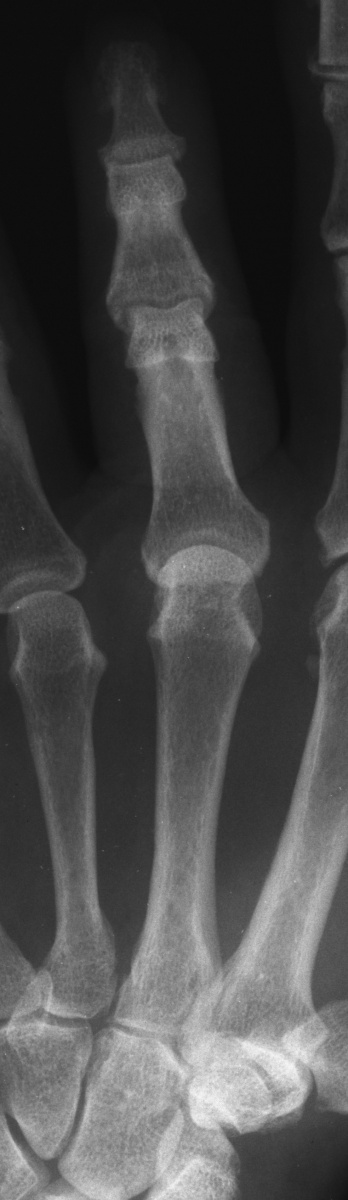

This 75 year old healthy woman had a sudden event reaching into a drawer two days ago. Since then, she could not straighten her middle MCP.

Standard AP Xrays were unremarkable.